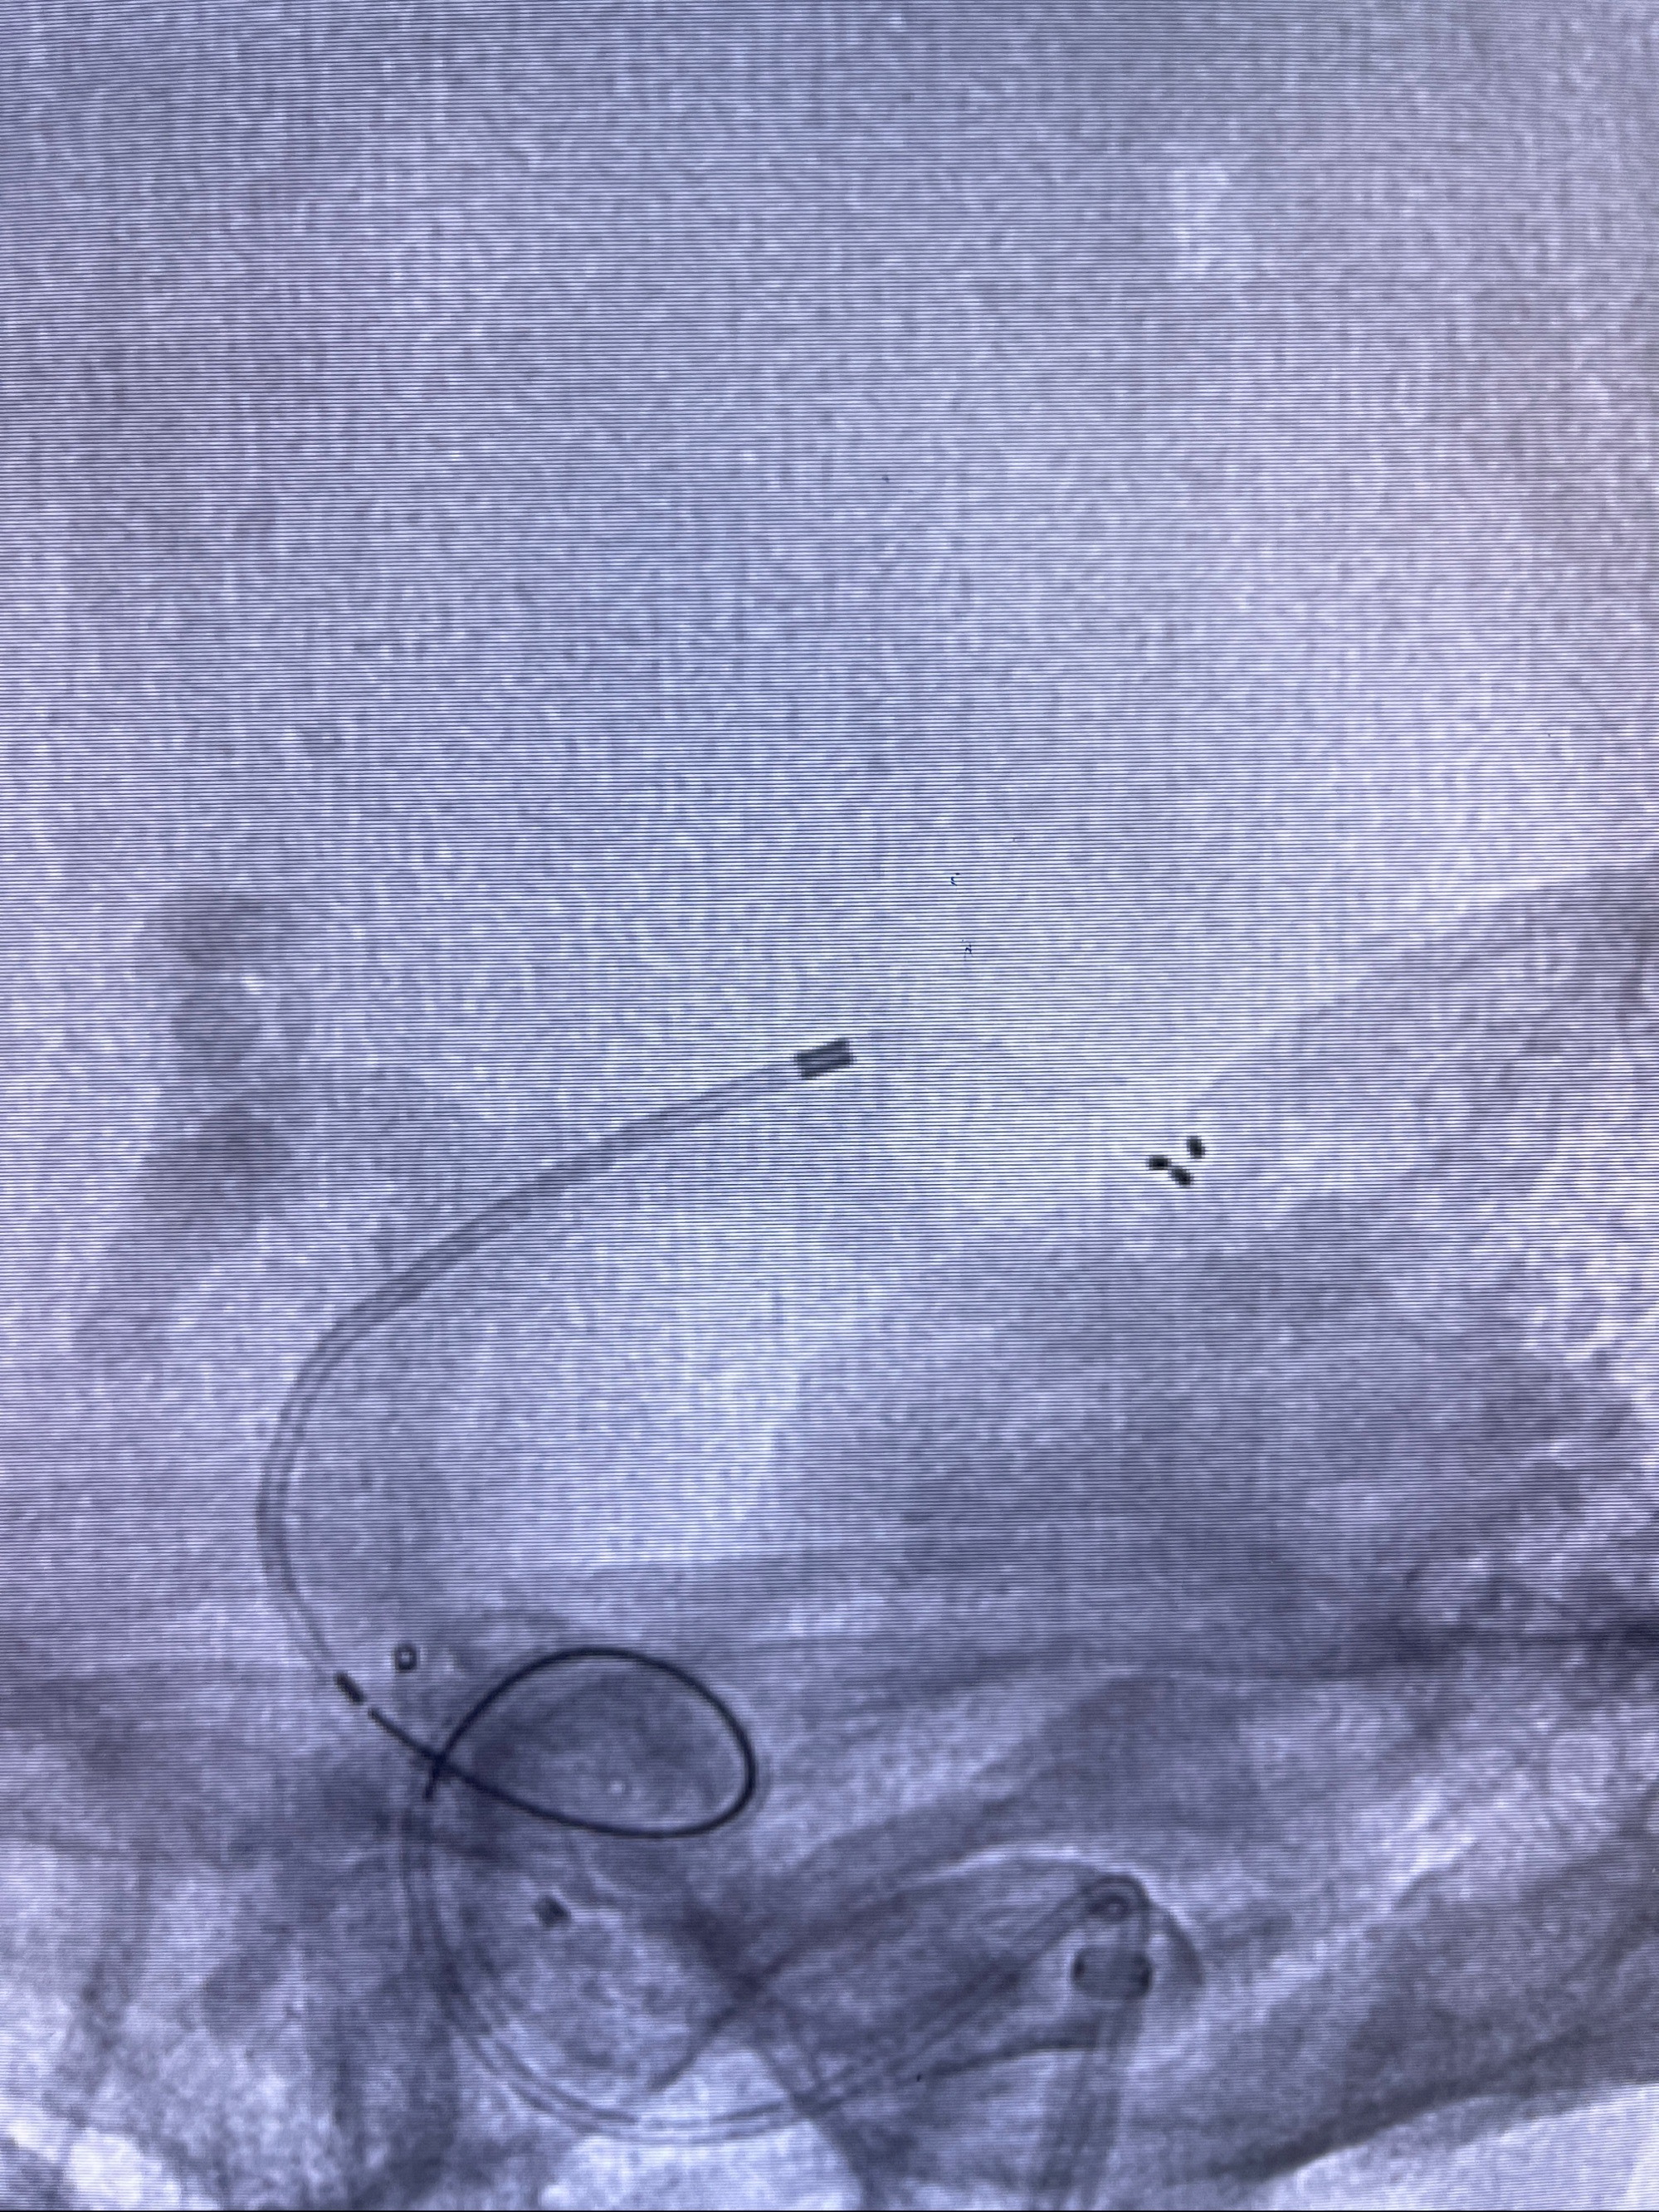

2023-08-14DSA:

左侧大脑中动脉动脉瘤,约2.6-2.8-3.4-2mm大小(瘤颈部、瘤体部、瘤高)